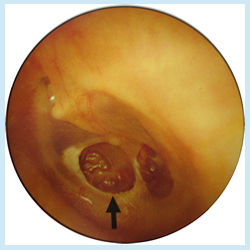

鼓膜に穴があき、耳だれが反復もしくは持続して出現し、また難聴が認められます。普段は耳の痛みはないか、あってもそれほど強くありませんが、急性化膿すると痛みが強くなります。ひどい場合には、頭痛や発熱を起こすこともあります。

慢性中耳炎は放置するとめまい、顔面神経麻痺、髄膜炎(脳膜炎)、脳膿瘍(のうのうよう:脳にうみの袋ができる)を合併したり、また真珠腫性中耳炎(しんじゅしゅせいちゅうじえん:耳の奥に白い塊ができ、骨を破壊しながら増殖していく困った中耳炎。手術が必要)など恐い病気になる場合があります。